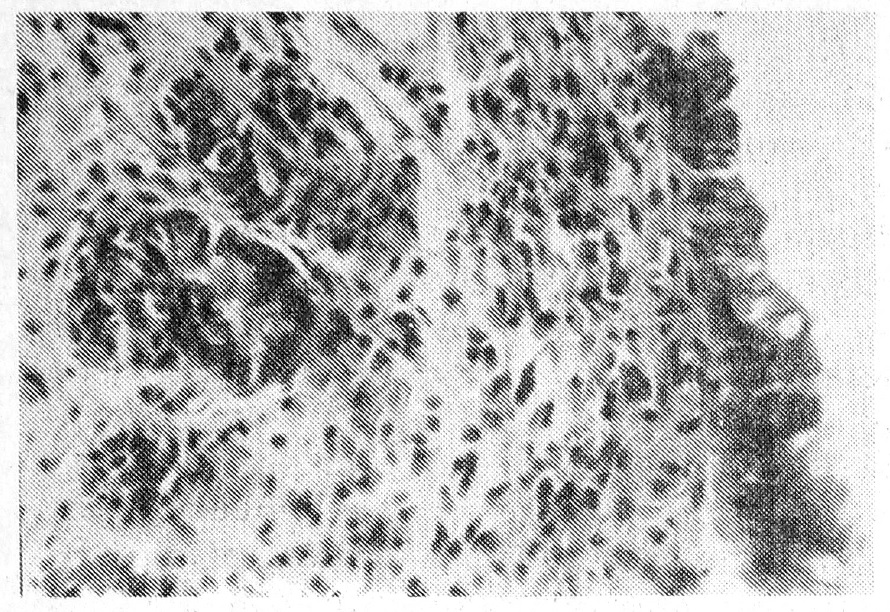

Во 2-й группе (у 3) при морфологическом исследовании биоптатов преобладала атрофия слизистой оболочки с очаговой десквамацией поверхностного эпителия и вместе с тем отмечалась гиперпродукция слизи в сохранившихся эпителиальных клетках. В строме имели место склероз и очаговая лимфоидно-гистиоцитарная инфильтрация (рис. 4). Мононуклеарная клеточная реакция в слизистой оболочке свидетельствовала о местных иммуноморфологических изменениях, отражающих гиперчувствительность замедленного типа.

Рис. 4. Микрофото гистологического препарата больной М., 53 лет, из области стриктуры сигмовидной кишки. Деформация желез в склерозированной и атрофированной слизистой оболочке. Лимфогиститоцитарная инфильтрация. Окраска гематоксилин-эозином.